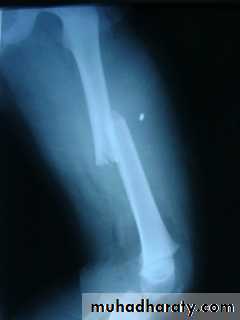

Femoral shaft fracture

Surgery – orthopedic – 5th stage – Dr. hishamThis fracture occurs at any age, it is common especially in young adults, and usually results from a high energy injury, such as

( car accident , fall from height).

X-ray :

Shows the type of fractures, and displacement. The x-ray should include the hip and knee and x-ray of pelvis to avoid missing segmental fractures, knee injuries, fractures of neck of femur, dislocation of hip, fractures of acetabulum and pelvis.